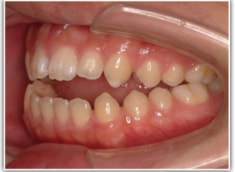

開咬(かいこう:オープンバイト)ケース

治療法:表の矯正(T21ブラケット)

(インプラントアンカーや外科矯正は行わず、エラスティックと機能訓練のみ)

治療後(2年2ヶ月後)